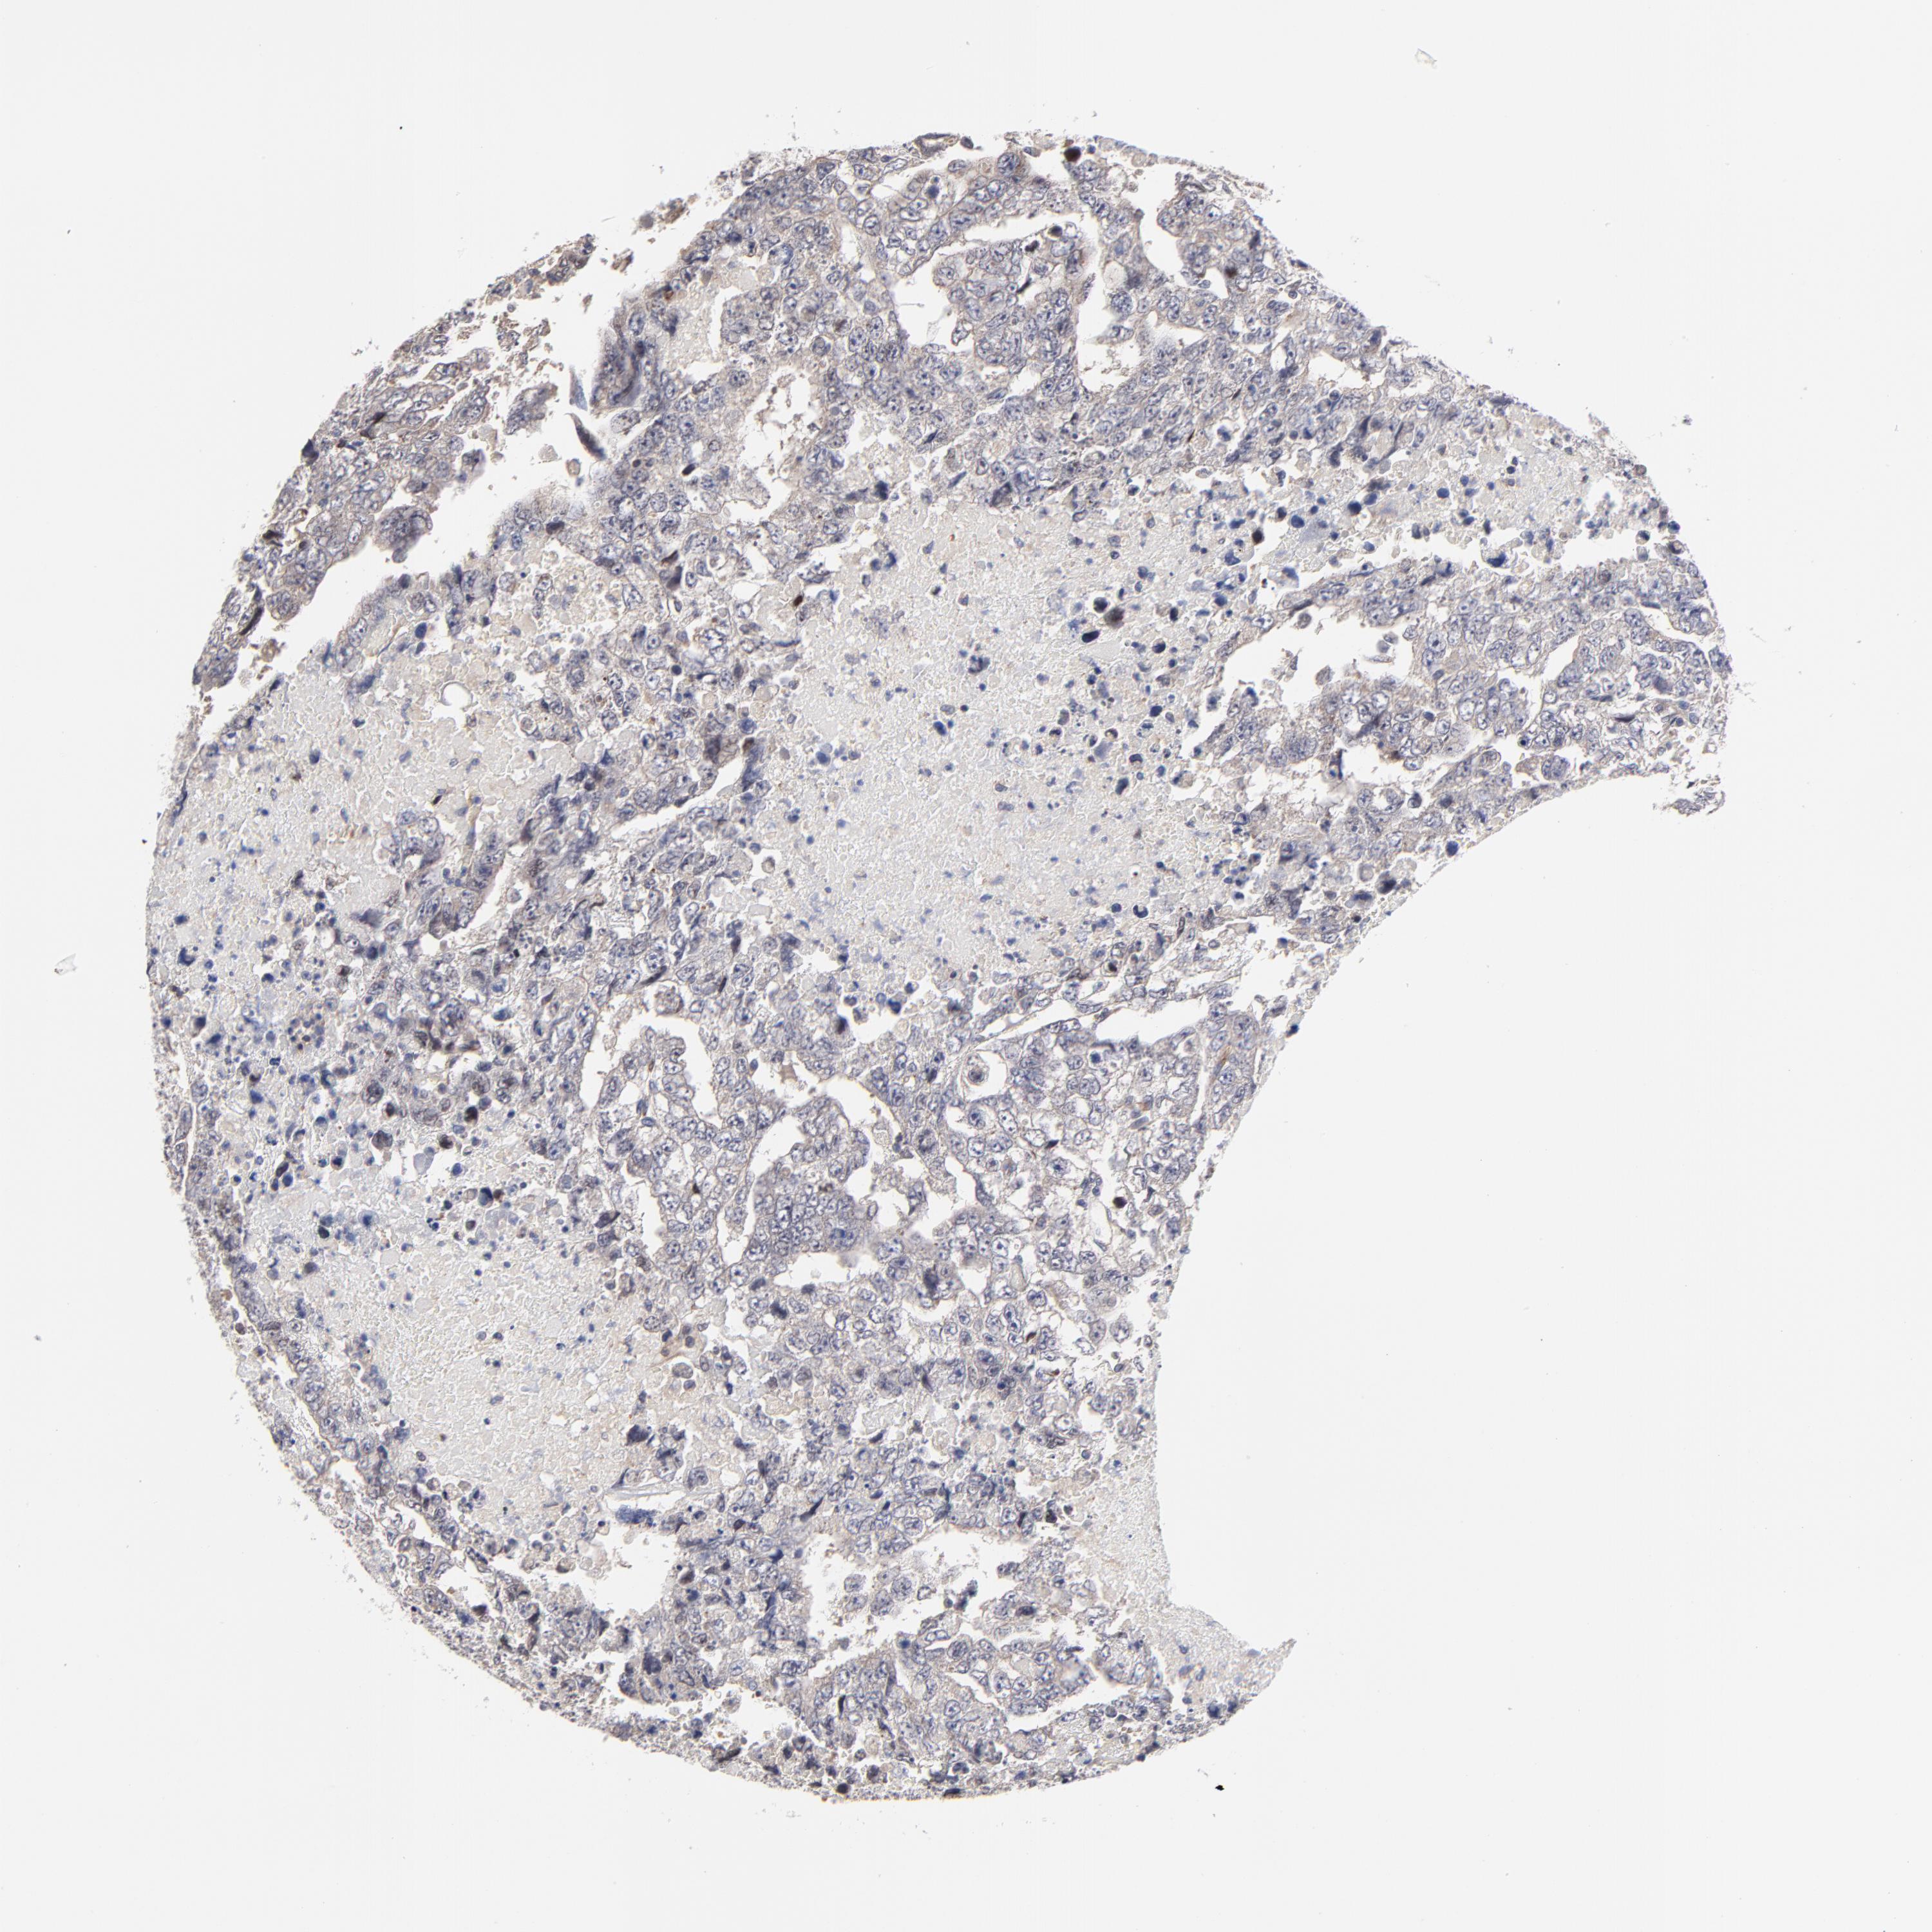

TESTIS CANCER - Protein expressioni

A mouse-over function shows sample information and annotation data. Click on an image to view it in a full screen mode. Samples can be filtered based on level of antibody staining by selecting one or several of the following categories: high, medium, low and not detected. The assay and annotation is described here.

Note that samples used for immunohistochemistry by the Human Protein Atlas do not correspond to samples in the TCGA dataset.

Antibody stainingi

Antibody staining in the annotated cell types in the current human tissue is reported as not detected, low, medium, or high, based on conventional immunohistochemistry profiling in selected tissues. This score is based on the combination of the staining intensity and fraction of stained cells.

Each image is clickable and will lead to virtual microscopy that enables deeper exploration of all samples and also displays staining intensity scores, fraction scores and subcellular localization as well as patient and tissue information for each sample.

Antibody HPA003319

Staining

High

Medium

Low

Not detected

Intensity

Strong

Moderate

Weak

Negative

Quantity

>75%

75%-25%

<25%

None

Location

Nuclear

Cytoplasmic/membranous

Cytoplasmic/membranous,nuclear

Carcinoma, Embryonal, NOS

Seminoma, NOS